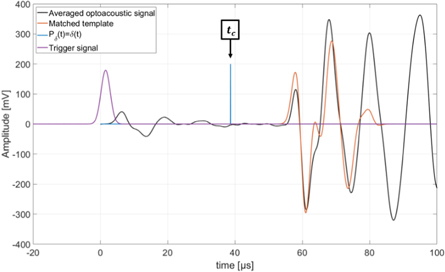

Additionally to the setup parameters, identical signal-processing was applied for the optoacoustic calibration measurement. This includes the generation and the matching of a template for which it was ensured to use the numerically identical temporal heating function and TIR(t). In contrast to the ionoacoustic measurements, the energy distributions and therefore also Pδ (t) was assumed to be delta-shaped as all photons are absorbed on the thin (50 μm) aluminium foil target. The evaluation process for the optoacoustic measurement is illustrated in figure 11.

Figure 11. Optoacoustic signal generated by the laser absorption on the aluminium foil target (black). The optoacoustic template (orange) is matched to the signal and the position of Pδ (t) = δ(t) is marked as the calibration time tc . Additionally the trigger signal (purple) is plotted. The starting time t = 0 s is chosen to match the 50% mark of the rising flank of the Gaussian pulse.

Download figure:

Standard image High-resolution imageThe template (orange) generated for the evaluation of the optoacoustic signal (black) is matched to the signal using the corresponding correlation function and the position of Pδ (t) = δ(t) (blue) relative to the template is known from the template generation. This time is defined to be the calibration time tc . This time has no direct physical meaning and is in particular not equal to the time of flight of the acoustic signal from its source at the aluminium foil target to the hydrophone. However, the calibration time enables a comparison to ionoacoustic measurements. Note that a comparison between optoacoustics and ionoacoustics is not self-evident as for the raw signals the different contributions from the different Pδ (t) cause different signal shapes. The comparison is only made possible by the calculation of the position of the individual Pδ (t) as within Pδ (t) the corresponding point of the dose deposition is known (see figure 6).

Figure 13. Pδ (t) obtained from the ionoacoustic measurement using 126 MeV protons and a dose of 29 Gy (black). Additionally the calibration time is plotted in blue.

Download figure:

Standard image High-resolution imageThe calibration time is indicated in blue and Pδ (t) as evaluated from the ionoacoustic measurement with 126 MeV protons (see figure 8) is shown in black, while its maximum position is indicated by the black dashed line. Their temporal difference is calculated to be ΔtL = 0.80 μ s ± 0.07 μs, where the indicated uncertainty was calculated in equation (6). This temporal difference is converted to a difference in distance according to equation (9) yielding a spatial offset between the Bragg peak and the calibration location of ΔxL = 1.23 ± 0.10 mm. This spatial offset is used to mark the Bragg peak position in the ultrasound image showing the irradiated region of the phantom using the integrated scale bar intrinsic to every ultrasound image (see figure 14).